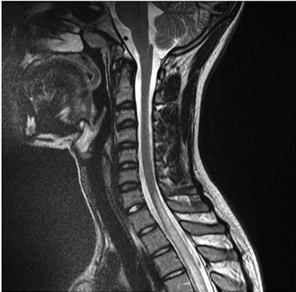

Paciente de 29 anos, sexo feminino, chega ao pronto atendimento apresentando fraqueza em membros inferiores, com três dias de evolução, que se associou à sensação de urgência urinária e constipação. Iniciou o quadro com alteração de sensibilidade nos membros inferiores e, no momento da admissão, não conseguia mais deambular. Na história pregressa, a paciente apresentava um quadro de artralgia e febre. No exame neurológico, entre outros achados, apresenta nível sensitivo em T2. Nos exames laboratoriais, observou-se pancitopenia, anti-DNA e anti-Sm positivos. A ressonância magnética da coluna cervical apresentou a seguinte imagem:

Enunciado 1991672-1

Em relação ao caso apresentado, é correto afirmar: